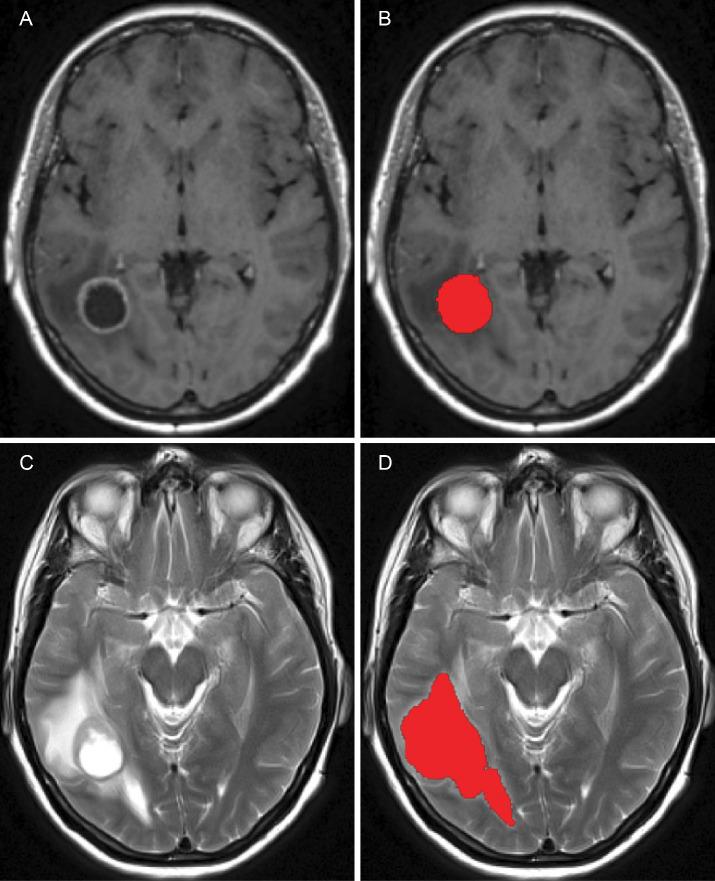

Glioblastoma multiforme (GBM), the most aggressive primary brain tumour, exhibits low survival rates due to its rapid growth, infiltrates surrounding brain tissue, and is highly resistant to treatment. One major challenge is oedema infiltration, a fluid build-up that provides a path for cancer cells to invade other areas. MRI resolution is insufficient to detect these infiltrating cells, leading to relapses despite chemotherapy and radiotherapy. In this work, we propose a new multiscale mathematical modelling method, to explore the oedema infiltration and predict tumour relapses. To address tumour relapses, we investigated several possible scenarios for the distribution of remaining GBM cells within the oedema after surgery. Furthermore, in this computational modelling investigation on tumour relapse scenarios were investigated assuming the presence of clinically relevant chemo-radio therapy, numerical results suggest that a higher concentration of GBM cells near the surgical cavity edge led to limited spread and slower progression of tumour relapse. Finally, we explore mathematical and computational avenues for reconstructing relevant shapes for the initial distributions of GBM cells within the oedema from available MRI scans. The results obtained show good overlap between our simulation and the patient's serial MRI scans taken 881 days into the treatment. While still under analytical investigation, this work paves the way for robust reconstruction of tumour relapses from available clinical data.

多形性胶质母细胞瘤(GBM)是最具侵袭性的原发性脑肿瘤,因其生长迅速、浸润周围脑组织且对治疗高度耐药,导致生存率较低。一个主要挑战是水肿浸润,即液体堆积,为癌细胞侵入其他区域提供了途径。磁共振成像(MRI)分辨率不足以检测这些浸润细胞,导致尽管进行了化疗和放疗仍会复发。在这项工作中,我们提出了一种新的多尺度数学建模方法,以探索水肿浸润并预测肿瘤复发。为了解决肿瘤复发问题,我们研究了手术后水肿内残留GBM细胞分布的几种可能情况。此外,在这项关于肿瘤复发情况的计算建模研究中,假设存在临床相关的放化疗,数值结果表明手术腔边缘附近较高浓度的GBM细胞会导致肿瘤复发的扩散受限和进展缓慢。最后,我们探索从可用的MRI扫描重建水肿内GBM细胞初始分布的相关形状的数学和计算途径。获得的结果显示我们的模拟与治疗881天时患者的系列MRI扫描之间有良好的重叠。虽然仍在进行分析研究,但这项工作为从可用临床数据中可靠地重建肿瘤复发铺平了道路。